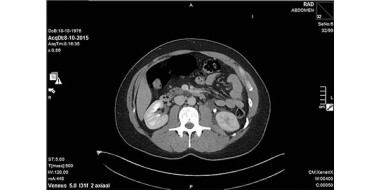

Henk, 2 jaar, komt met zijn moeder op het spreekuur. Zeven dagen geleden had hij koorts en sinds vier dagen heeft hij kleine vlekjes op de huid. Deze begonnen op de billen en bovenbenen, maar zijn sinds eergisteren over het hele lichaam verspreid. Bij navraag blijken er ook…